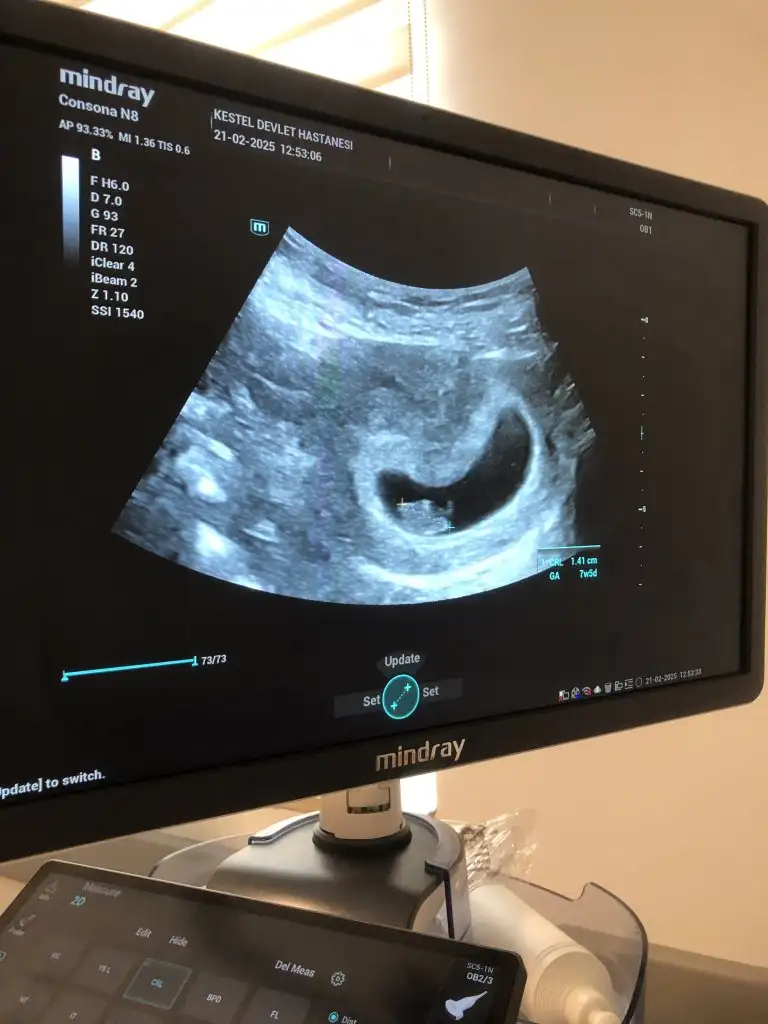

Bugün ilk muayeneye gittim kızlar. Aslında 8 haftayı geçtik ama 7+5 gösteriyordu. Birde kese şekline göre cinsiyet tahmini varmış doğru mu sizce. Tahmini olan varsa çok sevinirim 🥰💋

Bugün ilk muayeneye gittim kızlar. Aslında 8 haftayı geçtik ama 7+5 gösteriyordu. Birde kese şekline göre cinsiyet tahmini varmış doğru mu sizce. Tahmini olan varsa çok sevinirim 🥰💋Eki Görüntüle 3548048

Merhaba canim maşallah 🧿Bebişini sağlikli bir sekilde kucağina alirsin inşallah senin tabloda 29 aralik değil miydi son adet tarihi 7+5 günlük olmasi gerekiyor zaten doğru çikmiş benim sat tarihim de 30aralik 7+4 ordan biliyorum♥️ aramizda bir gun var bende yarin gidicem inşallah kalp atişinida duydunmu kuzum🧿♥️

Maşallah canım cam gibi çıkmış devlet olmasına rağmen ben acil değiştirmem lazım hastaneyi makineleri kötü sanırım bide özel nere bebek nere kese belli değil